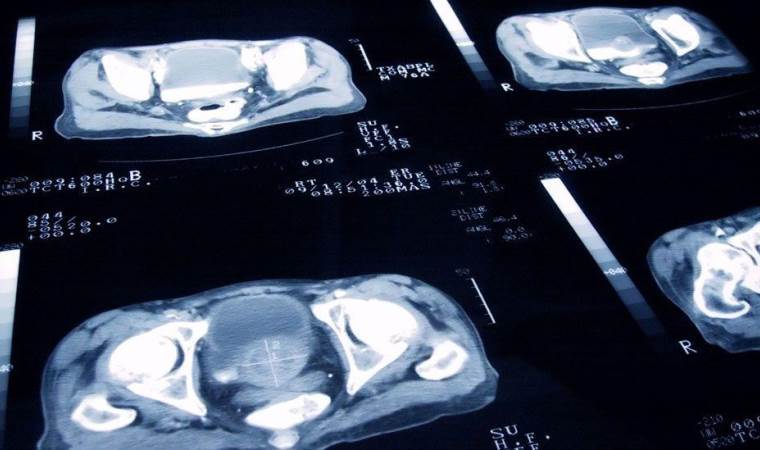

Akciğer Kanserinde tedavi belirlemesinde en önemli faktörün, kanserin tipi ve evresi olduğunu vurgulayan Koşucu, sözlerini şöyle tamamladı; “Akciğer kanseri, görüntüleme yöntemleri ile tespit edildikten sonra kesin tanı biyopsi sonrasında konur. Tedavi belirlemesinde en önemli faktör kanser tipi ve evresidir. Uygun hastalarda cerrahi yöntemle kanserin bulunduğu akciğer veya akciğer bölümü çıkartılabilir. Cerrahi işleme elverişli olmayan hastalara ise kemoterapi ve/veya radyoterapi uygulanabilmektedir. Akciğer kanserinden korunmak için risk faktörlerinden mümkün olduğunca uzak durmak, sağlıklı yaşam alışkanlıkları geliştirmek gerekmektedir.”